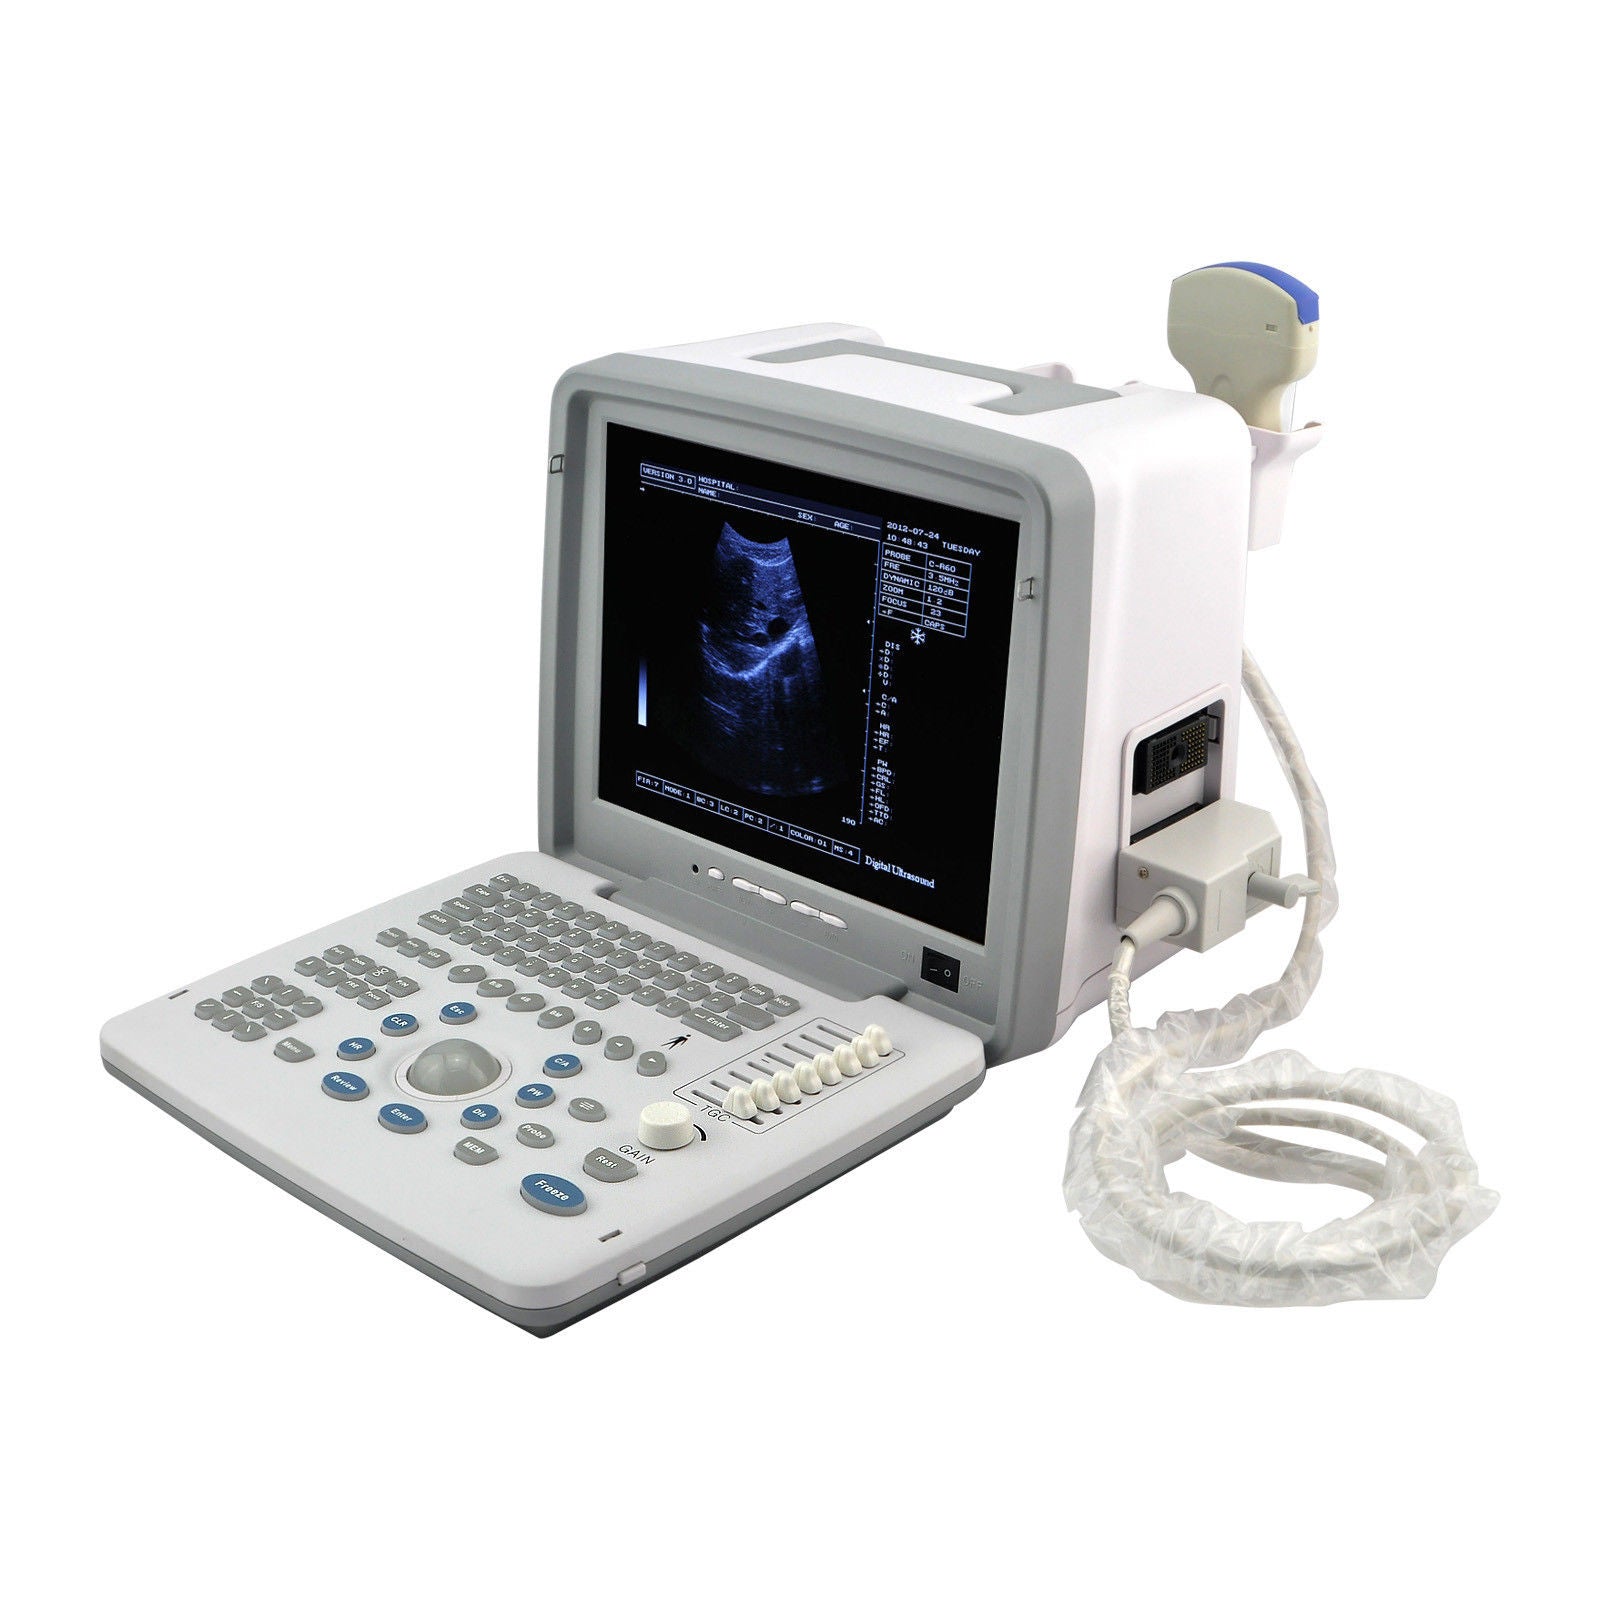

Model: RUS-9000B

Display: 12-inch SVGA high resolution monitor

Versatility in Medical Settings

The portable ultrasound scanner is an essential tool for various medical environments. It offers the flexibility to conduct scans in clinics, hospitals, and even at home. Doctors and healthcare professionals appreciate its compact design, which facilitates ease of transport. Furthermore, the inclusion of both convex and transvaginal probes expands its usability, allowing practitioners to perform different types of examinations efficiently.

High-Quality Imaging

This 12-inch digital ultrasound scanner provides exceptional image quality, ensuring accurate diagnoses. The advanced technology utilized in this device captures clear and detailed images, which are crucial for assessing patient health. Additionally, the intuitive interface and user-friendly controls help medical staff conduct scans swiftly, thus improving patient flow without compromising quality.

Cost-Effective and Reliable Solution

Investing in a portable ultrasound scanner proves to be a cost-effective solution for many healthcare facilities. Its durability and reliability mean that it requires less frequent replacements, thus saving money over time. Moreover, because it combines functionality with portability, it ensures that healthcare providers can meet their patients' needs promptly, enhancing overall care delivery.